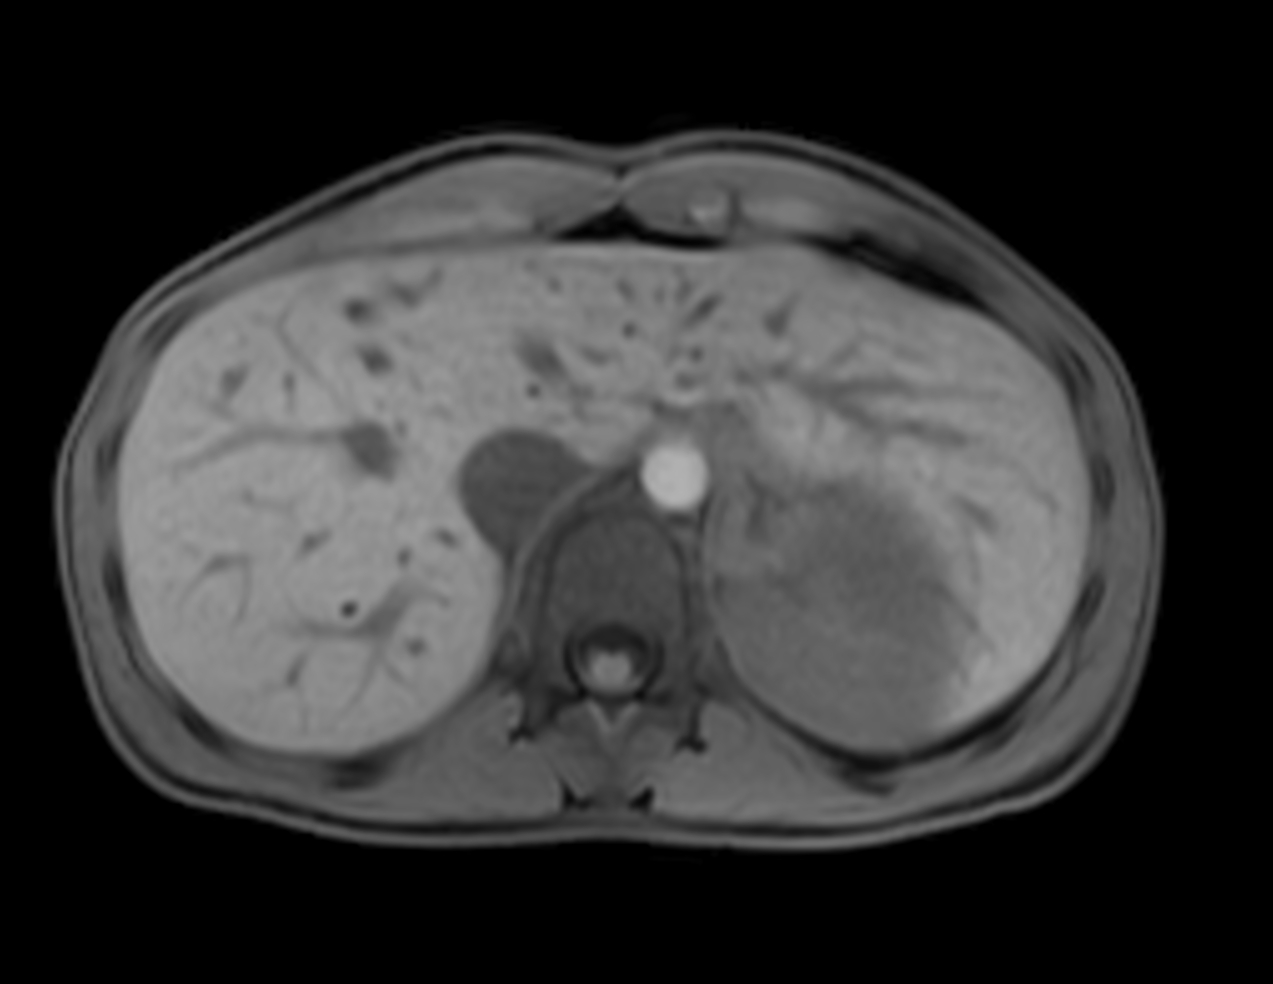

Axial mDIXON XD - T1w FFE (In Phase)